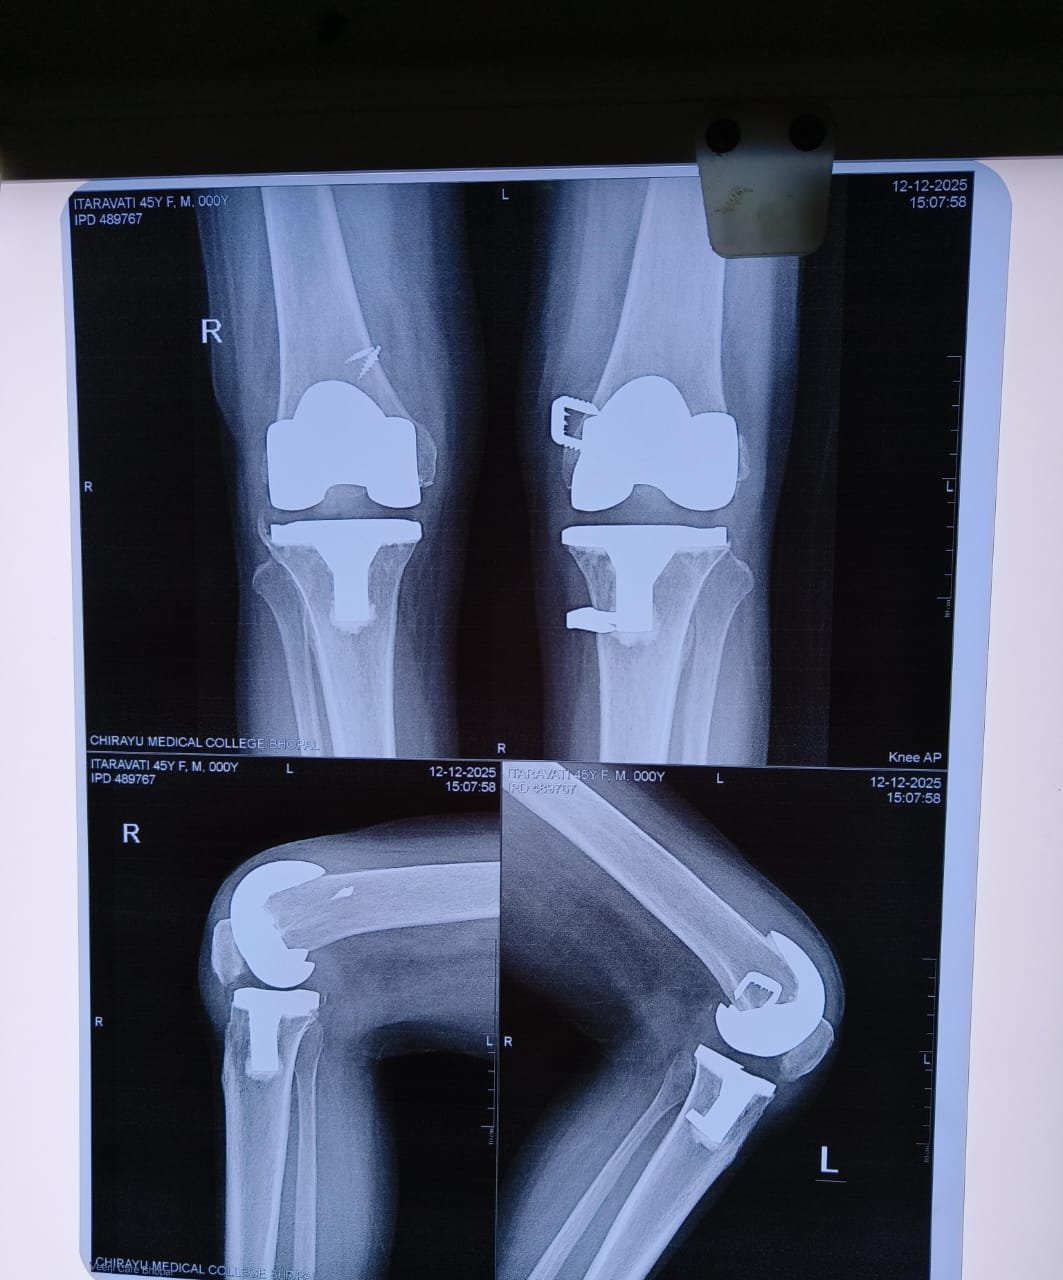

- Knee Replacement Surgery

- Robotic Joint Replacement